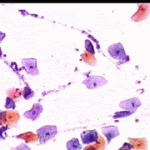

6.9.2002 Μετά από πάροδο διετίας επανέρχεται για προληπτικό έλεγχο.. Στο ιστορικό μικρο-υποτροπές κολπίτιδας, που ξεπερνούσε παροδικά με 3ήμερη χρήση Daktarin vag. supp. Το κολποσκοπικο εύρημα ήταν φυσιολογικό, ωστόσο το κυτταρολογικό επίχρισμα εμφάνιζε την τυπική πολυμορφία ερπητικών αλλοιώσεων.

4.8.2005 σε 2-3 οπτικά πεδία κυτταρολογικές ατυπίες που συνηγορούν για ερπητικές αλλοιώσεις ..

Στις 27.4.2010 εκ νέου σποραδική διακριτική κοιλοκυτταρική ατυπία και χαρακτηριστικές ατυπίες πυρηνων, που συνηγορούν, σε συνάρτηση με το ιστορικό, για ερπητικές αλλοιώσεις.